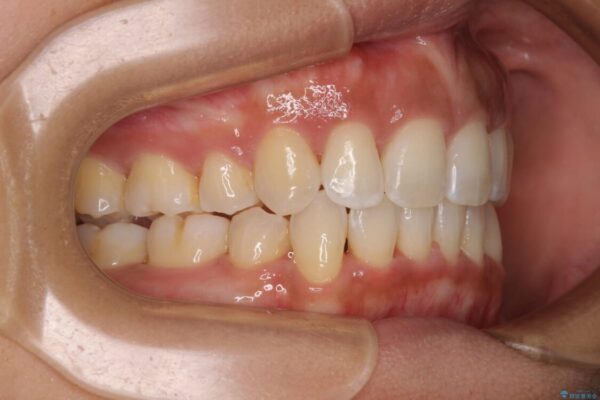

治療後

• 抜歯矯正で唇を閉じやすく 目立たないワイヤー装置 治療後画像

抜歯スペースに前歯を移動させることで歯の突出感が改善され、非常に唇が閉じやすい仕上がりとなりました。